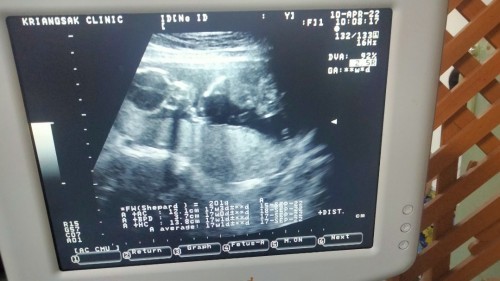

สอบถามหน่อยคะ กำหนดคลอดคือ20กันยาพอใส่ในแอปนี้มันขึ้นว่า16วีค5วัน แต่กับใบซาวด์ของหมอดูจากตัวเด็กคือ17วีค1วัน ตือเราควรเปลี่ยนให้ตรงกับใบซาวด์ไหมคะ หรือยึดตามกำหนดคลอดคะ#ขอคำแนะนำหน่อยค่ะ

ใบซาวนด์ประเมิณจากขนาดลูกค่ะ ว่าขนาดตามเกณฑ์ไหม ไม่ใช่อายุครรภ์นะคะ อายุครรภ์ในใบไม่ได้ระบุค่ะ ตรงมุมขวาบนคำว่า GA

บ้านนี้วัดศรีษะ กำหนดคลอด 7/10/65 วัดขนาดความยาวลำตัว กำหนดคลอด 11/10/65 เราควรยึดวันไหนแน่คะ 😄

3.7cm AC 12.1cmคะ